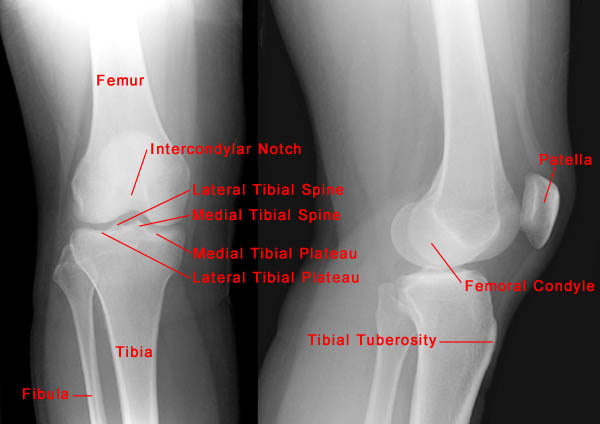

The following radiographs show the normal anatomy of the knee.

AP View Lateral View

• The knee is the largest joint in the body and consists of three articulations: medial tibiofemoral, lateral tibiofemoral and patellofemoral.

• Routine radiographic examination of knee trauma includes four projections: AP, lateral and two oblique views. A tunnel projection of the intercondylar notch and/or a sunrise view of the patella may be required depending on the injury.